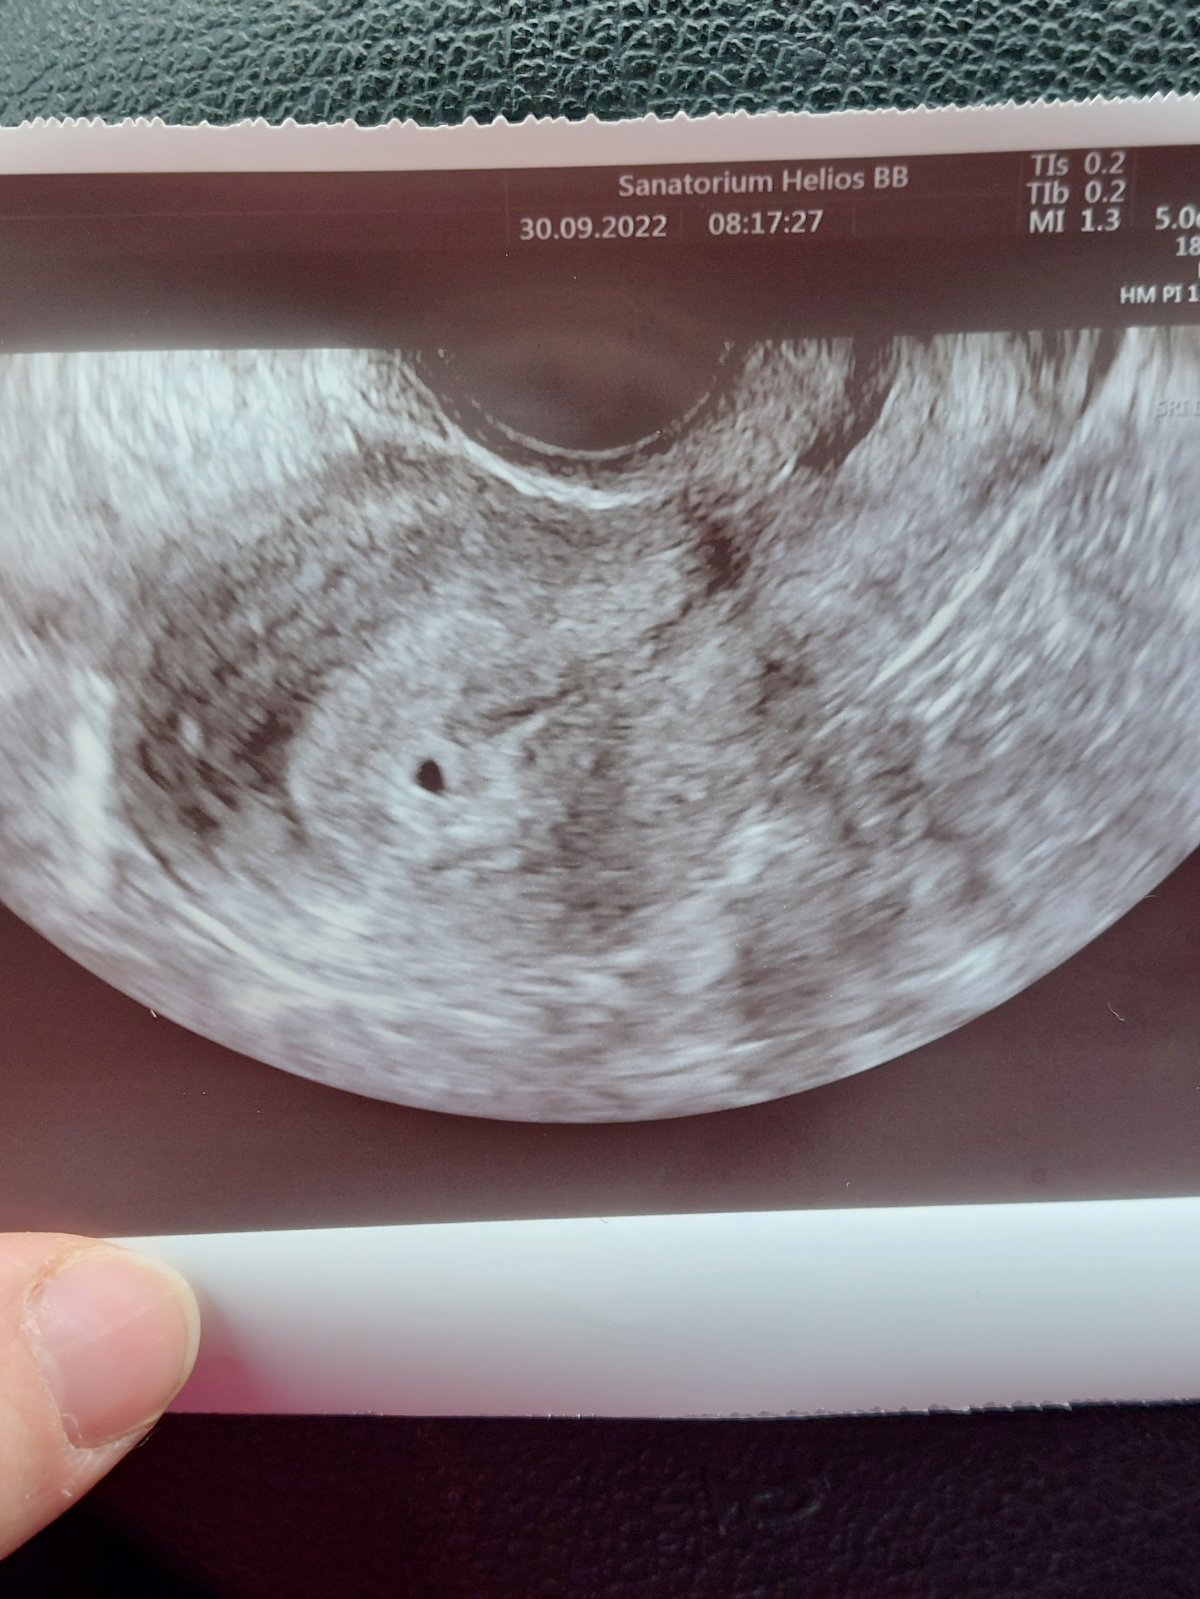

@jarrys ahoj ano dobre spravy. 😊😍Bolo vidno 3mm gestacny vacok. Svacova tam videla uz aj bodku ale ja ju na fotke este nevidim,tak len verim ze tam je. HCG 1368. A testy mam pozitivne riadne. Dalsiu kontrolu mam o tyzden v piatok 7.10 tak uz len nech sa pekne drzi 🙏🙏🙏